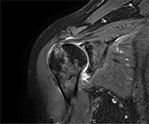

Пример МРТ правого плечевого сустава

Соотношение костей в суставе правильное. Головка плечевой кости и суставная впадина лопатки имеют типичную конфигурацию. Отмечается небольшое уплощение по типу импрессии головки плечевой кости в верхне-наружных отделах с перифокальным костным отеком. Внутрикостный очаг кистовидной перестройки в передне-внутренних отделах головки плечевой кости, диаметром 5 мм.

Ширина суставной щели не изменена (до 6 мм).

Значительное увеличение количества жидкости в полости сустава, по ходу сухожилия длинной головки бицепса, в субакромиально-субдельтовидной и субклювовидной сумках.

Суставной хрящ в передних отделах посттравматически разволокнен, истончен.

Суставная губа в передних и передне-нижних отделах деформирована, отслоена от гленоида.

Отмечается повреждение нижней глено-хумеральной связки в плечевой порции, растяжение капсулы сустава.

Акромиально-ключичное сочленение правильной конфигурации, расстояние между суставными поверхностями в пределах нормы (до 10 мм), субакромиальное пространство не сужено (9 мм).

Субтотальный разрыв сухожилия надостной мышцы и частичный разрыв сухожилия подлопаточной мышцы.

Сухожилие двухглавой мышцы плеча интактно, нормальной структуры (ширина 4-6 мм), располагается в межбугорковой борозде.

Мягкие ткани плечевой области без особенностей.

ЗАКЛЮЧЕНИЕ по снимку МРТ плечевого сустава:

МР-картина повреждения суставной губы в передних и передне-нижних отделах по типу Банкарта, незначительная импрессионная деформация головки плечевой кости с перифокальным костным отеком, субтотальный разрыв сухожилия надостной мышцы и частичный разрыв подлопаточной мышцы, значительный суставной выпот, повреждение нижней гленоидально-плечевой связки, субакромиально-субдельтовидный и субклювовидный бурсит.

Рекомендована консультация травматолога.